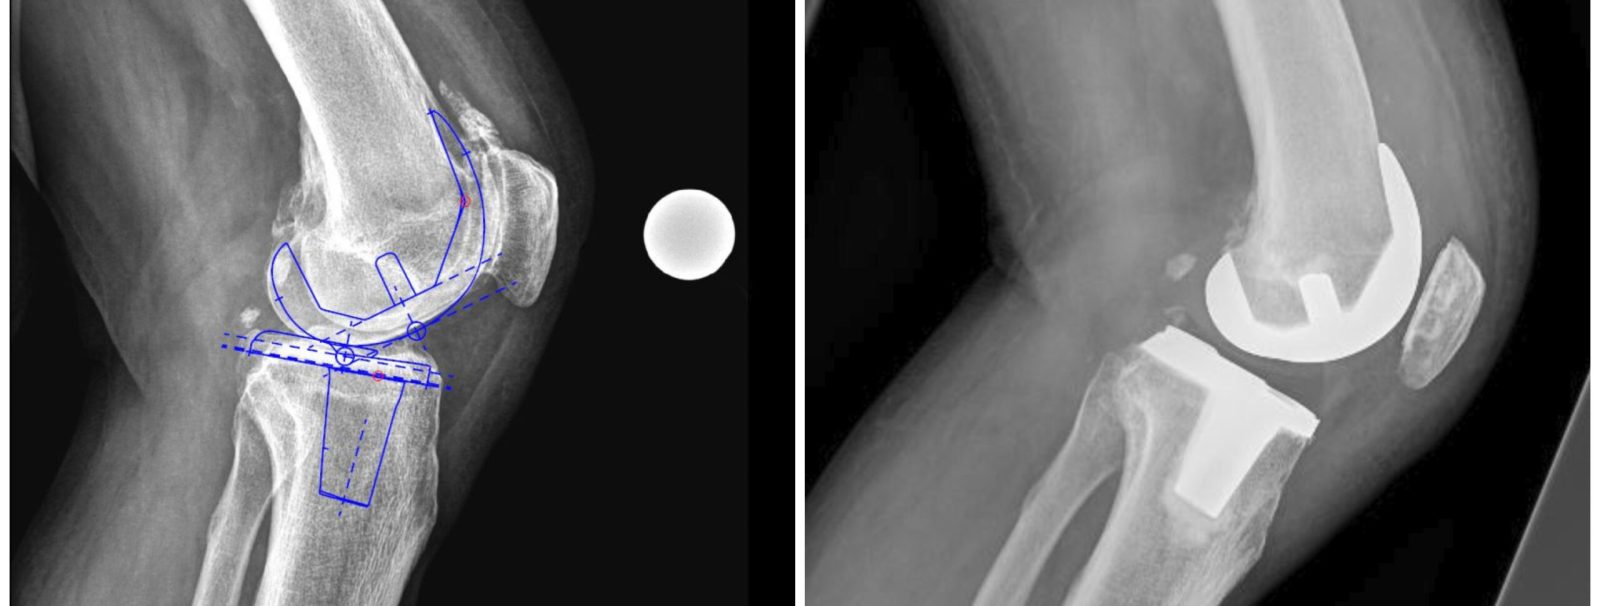

Analogamente alla progettazione di un ingegnere per poter avviare la costruzione di un edificio, l’atto chirurgico non può prescindere da un minuzioso planning preoperatorio, condotto sia su film radiografico che in modalità digitale mediante sofisticati software di pianificazione.

La buona riuscita della procedura chirurgica sarà la risultante di un’accurata pianificazione e della sua fedele riproduzione intraoperatoria